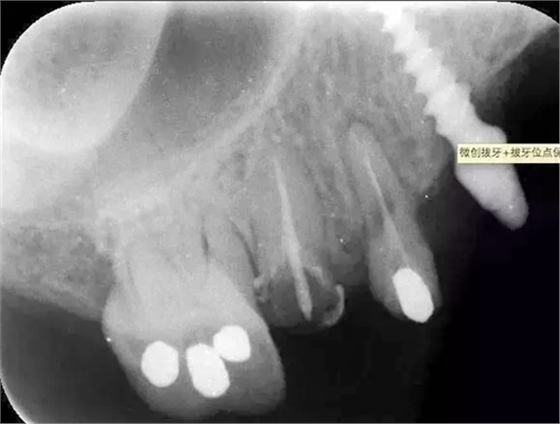

處理:14、15微創(chuàng)拔牙+拔牙位點(diǎn)保存術(shù)。

?術(shù)前的x線根尖片